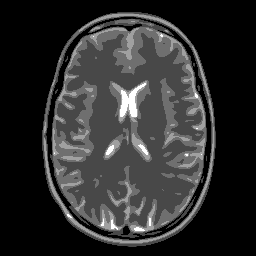

Concerning the real MRI data we compare IL and FNCR algorithms in the reconstructions of the brain image (T3 test), represented in figure 8. We report in table 6 the results obtained by reconstructing the noiseless data undersampled by , , masks.